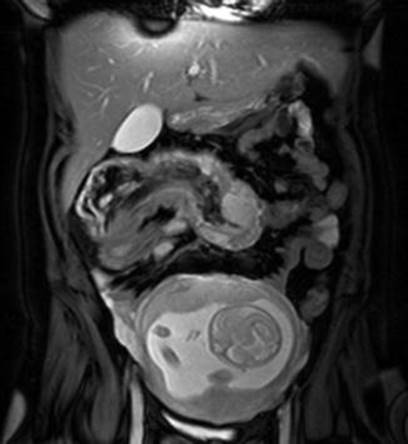

Abdominal sonography can make the diagnosis of an intussusception in an adult when the characteristic sign of a “target-like” lesion or “bull’s eye” lesion is shown, similar to the CT findings, and is sometimes enough for the definitive diagnosis [83]. The classic features of intussusception include “target,” “doughnut,” or “crescent-in-doughnut” signs on a transverse view and the “pseudokidney” sign in the longitudinal view (Fig. 7.8), or multiple concentric rings of intussusceptum (Fig. 7.9) or multiple concentric vascular signals in thickened intussuscipiens (Fig. 7.10) [72, 73, 95–97]. The central echogenic area is produced by the mucosa of the intussusception, which is surrounded by a hypoechoic ring representing the walls of both the intussusceptum and the intussuscipiens [98]. This variability in appearance is largely due to the scanning level, the amount of intussuscepted mesentery, the degree of bowel wall edema, and the presence of a pathologic lead point and lymph nodes. Ultrasound is an operator-dependent technique whose utility may be limited by obesity and air in distended bowel loops.

Fig. 7.8

(a) Transverse abdominal sonography: in the left lower quadrant, a “bull’s eye” or “doughnut” image with an echogenic center and a translucent rim (arrows) is visible. (b) Longitudinal ultrasound scan showing the “pseudokidney” sign, representing the appearance of the intussusceptum and intussuscipiens (arrows) [73]

Intussusception is well diagnosed on abdominal CT, which shows a pathognomonic bowel-within-bowel configuration with or without contained fat and mesenteric vessels [99]. Intussusception appears as a sausage-shaped mass when the CT beam is parallel to its longitudinal axis but as a target-like mass when the beam is perpendicular to the longitudinal axis [66]. With the increasing use of ultrasound, CT, and improved methods for examining the small bowel, intussusception is currently diagnosed more frequently before operations (Fig. 7.11). Currently, instead of CT scan, MRI is used to eliminate ionizing radiation (Figs. 7.12 and 7.13).

Fig. 7.12

A 31-year-old woman at 23 weeks’ gestation with severe left-sided abdominal pain. Sagittal (a) and transverse (b) images show intussusception of small bowel in the left upper quadrant. Note dilated loops of small bowel and free fluid [100]

Fig. 7.13

Magnetic resonance image of intussusception in the epigastric region, with the gravid uterus inferior to and separate from the mass [81]